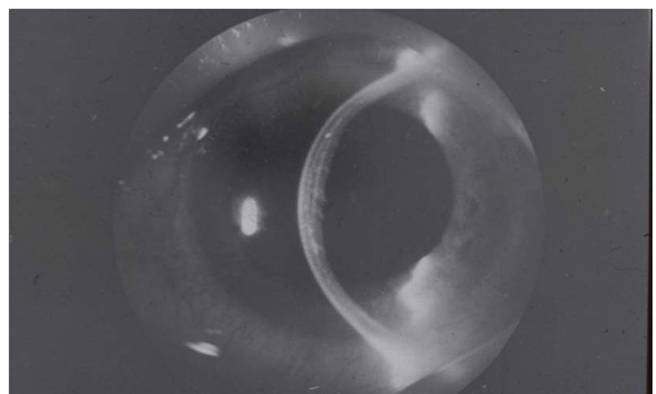

Рис. 8.2.11. Роговица и трансплантат прозрачны, незначительные складки десциметовой оболочки

Рис. 8.2.12. Трансплантат отдавливает задние слои роговицы в сторону передней камеры